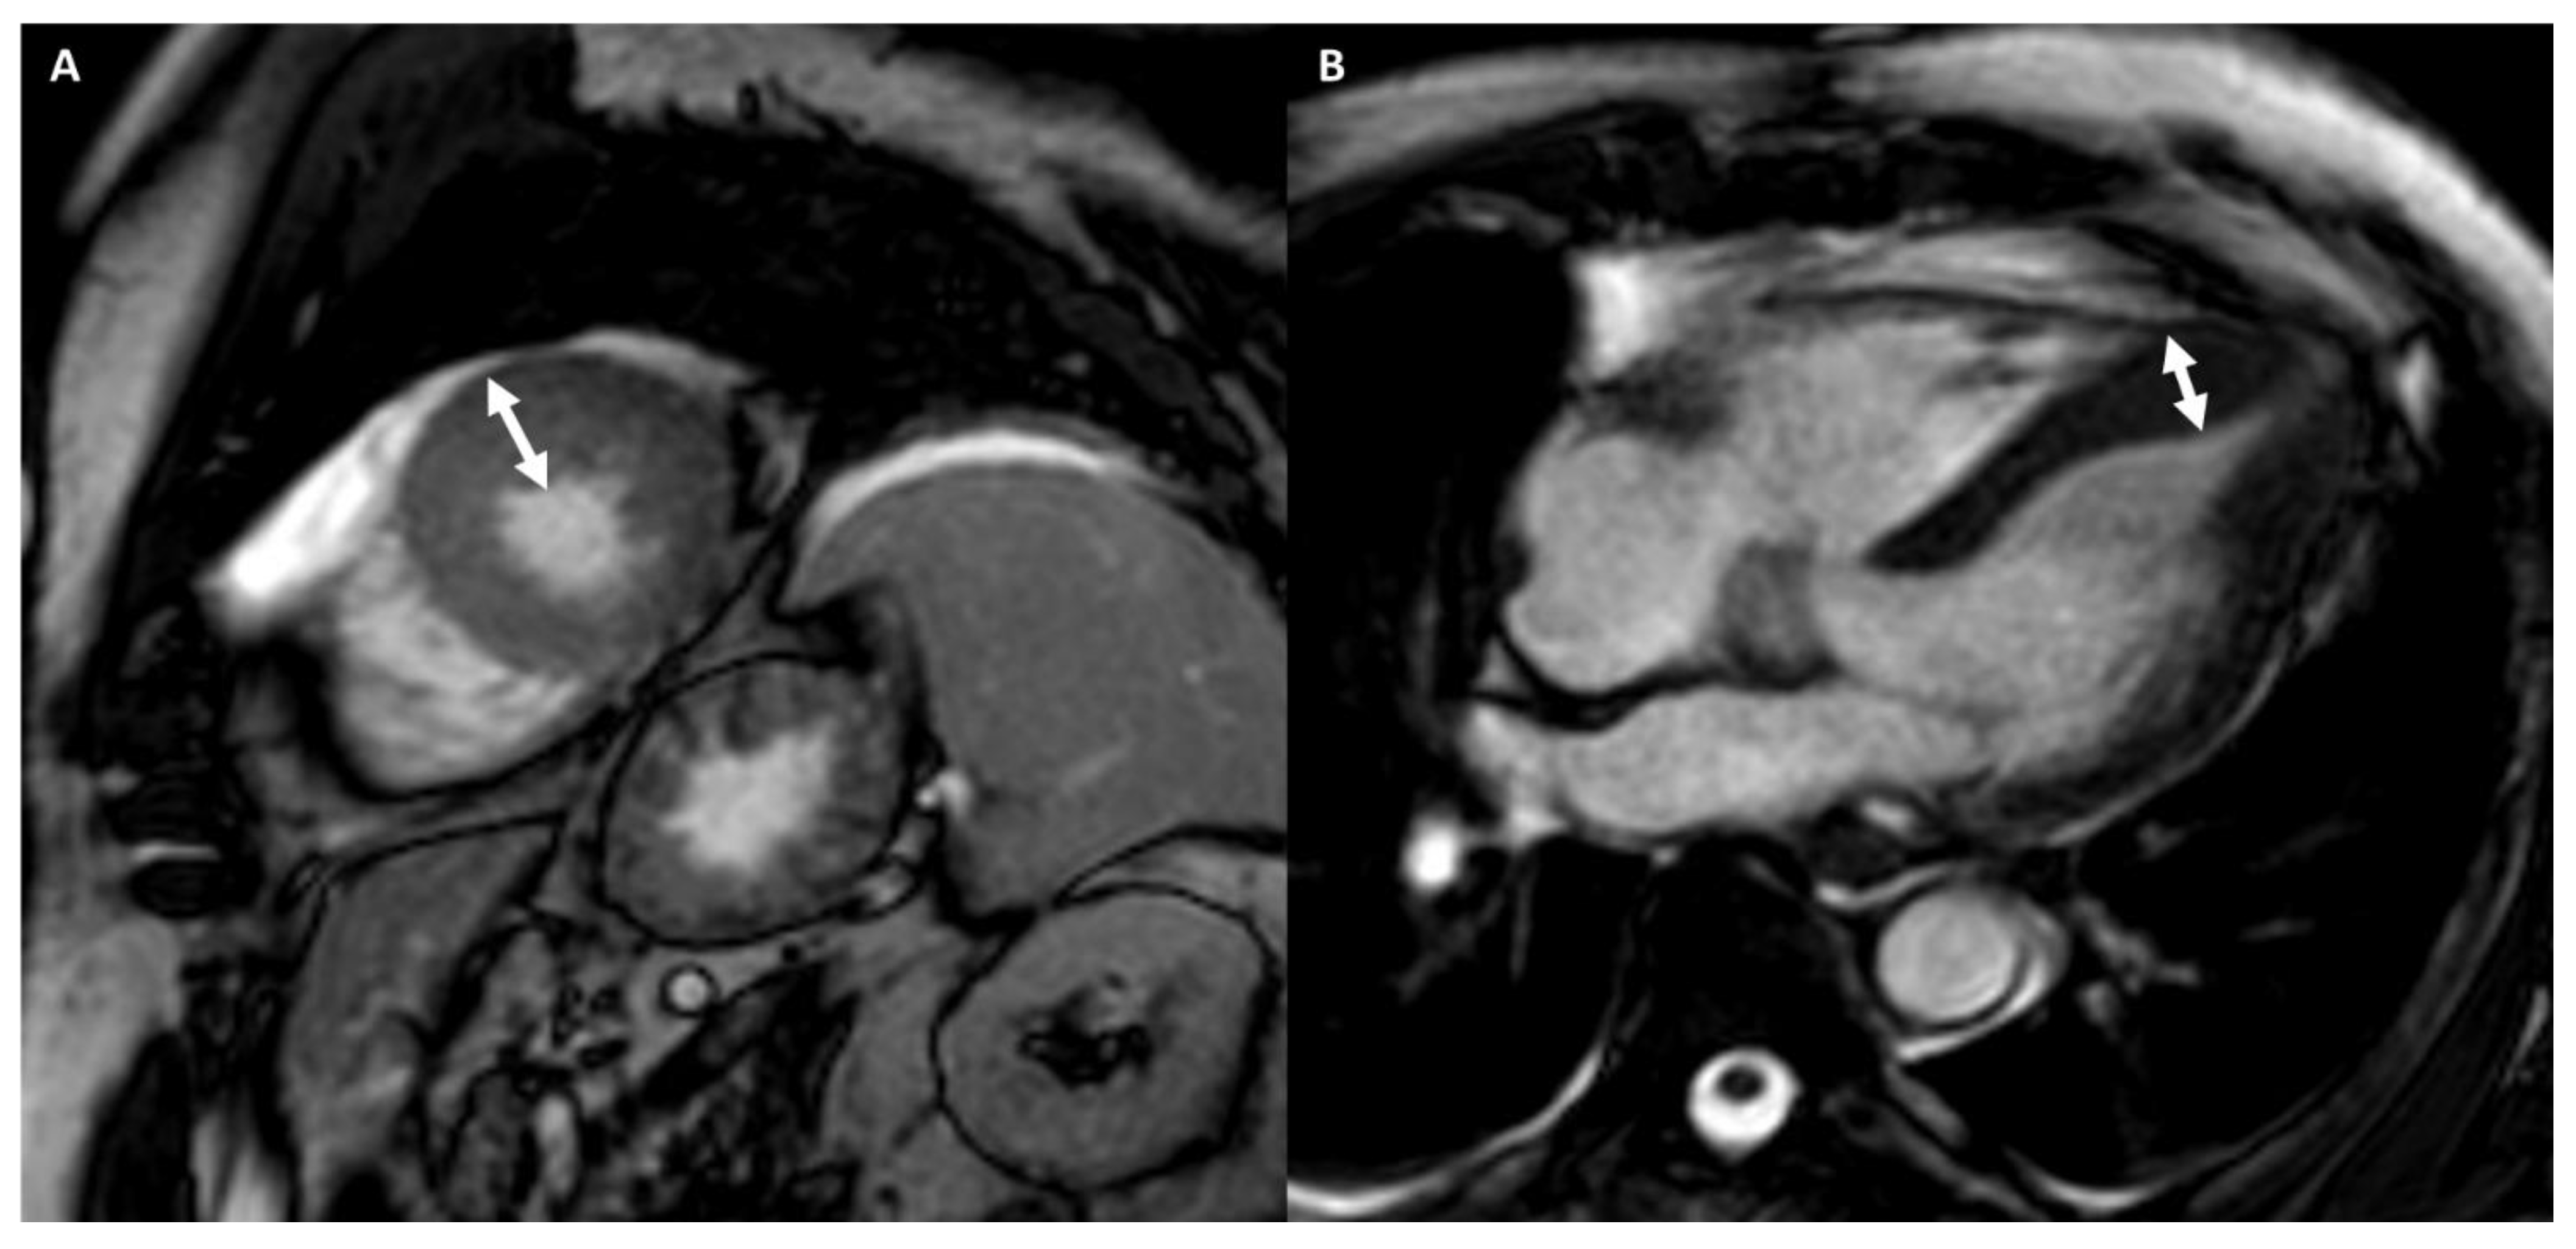

Arrhythmogenic Right Ventricular Cardiomyopathy

- Palumbo, P.; Cannizzaro, E.; Di Cesare, A.; Bruno, F.; Schicchi, N.; Giovagnoni, A.; Splendiani, A.; Barile, A.; Masciocchi, C.; Di Cesare, E. Cardiac magnetic resonance in arrhythmogenic cardiomyopathies. Radiol. Med. 2020, 125, 1087–1101. [Google Scholar] [CrossRef]

| LGE/LIE | |||||||

| Type | Linear | Patchy or massive | Linear | Linear | Linear | Linear | Linear or parchy |

| Layer | Mesocardial | Mesocardial | Mesocardial | Mesocardial | Subepicardial Mesocardial | Subepicardial | Subendocardial Mesocardial |

| Site | Interventricular juctions | Hypertrophic area; interventricular junctions | Septum; infero-lateral LV wall | Variable, not associated with NC area | Anterior RV wall | Infero-lateral LV wall | Circumferential; septum; lateral LV wall |